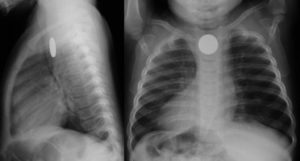

Монета на обзорной рентгенографии ребенка

Обычно уже в условиях стационара малышу назначаются такие процедуры, как рентген или эндоскопия ЖКТ, все зависит от результатов предварительного осмотра и возраста пациента. Исследования подобного рода помогут максимально быстро определить, в каком именно месте расположена проглоченная монета.

Доктор также поможет определить точное положение монеты в вашем ребенке с помощью рентгена, и вы можете быть уверены, что объект, который проглотил ваш ребенок, — это просто монетка и ничего больше.

- Рентген. Позволяет обнаружить местонахождение монеты;

В отличие от пластмассовых деталей монету легко отследить на рентгене.

Для правильного выбора тактики лечения важно выяснить, где именно она находится, поэтому родителям нужно либо вызвать скорую помощь, либо самостоятельно отправиться в приемное хирургическое отделение детской больницы (с проглоченными металлическими предметами нужно обращаться именно в хирургию, а не в отоларингологию) для проведения необходимых мероприятий.

Если рентгеновское исследование покажет, что монета находится у ребенка в пищеводе, то, скорее всего, вам предложат немедленно её удалить при помощи ФГДС. Инородное тело, застрявшее в пищеводе, может привести к разрыву его стенки – а это серьезное состояние, угрожающее жизни маленького человечка.

Ориентироваться только на эти признаки нельзя, потому что поведение некоторых детей не меняется вовсе. Точное местоположение монеты можно увидеть только на рентгене.